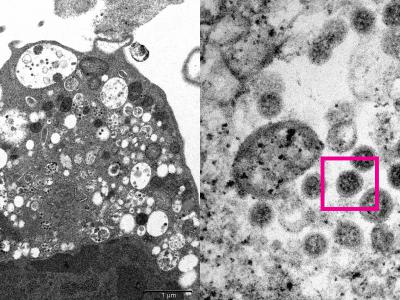

香港大学医学院发布电子显微镜下新冠病毒

香港大学医学院发布电子显微镜下新冠病毒奥密克戎Omicron变体的真实面貌(神秘的地...

香港大学医学院团队宣布成功从临床标本中

香港大学医学院团队宣布成功从临床标本中分离出Omicron变种病毒(神秘的地球uux.cn...